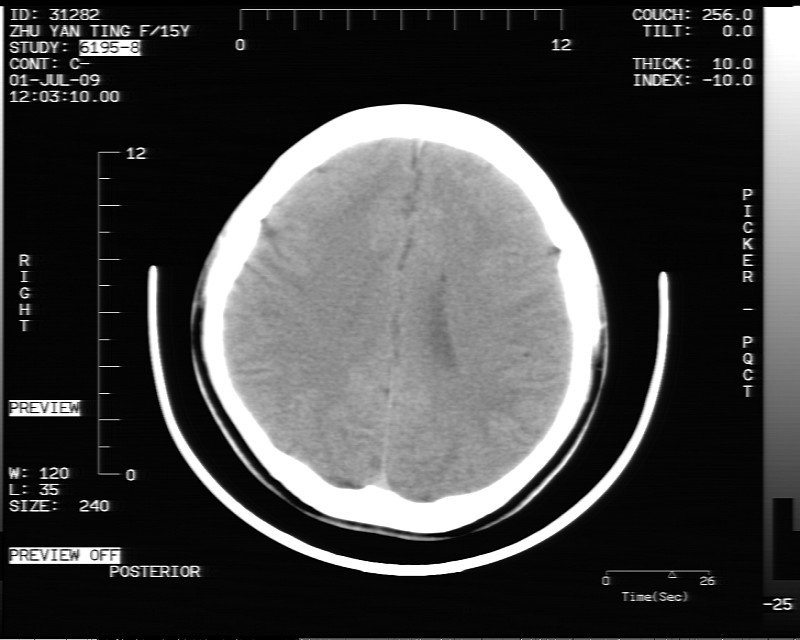

以下是引用余辉在2009-7-1 17:20:00的发言:[br]病变ct值-20至-80[br]考虑脑内脂肪瘤破裂,瘤主体应该在右侧桥小脑角池及鞍上池[br]鞍上池病灶面积较大,ct值应该能够测准,应此病灶应该就是脂肪密度,病灶密度有ct值-20至-80hu,为成熟脂肪密度,因此考虑脂肪瘤,也不除外其他含成熟脂肪的病灶[br]皮样囊肿密度应该稍高一点